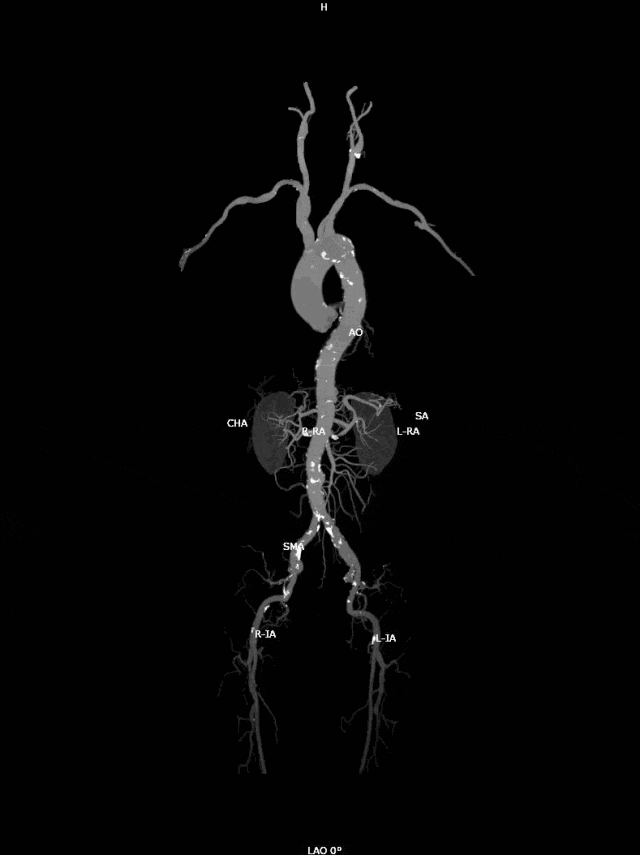

近日,吴爷爷因为慢性支气管炎急性发作,到奉城病院呼吸科入院诊治,入院时期进行CT查验,CT文告披露:主动脉弓部动脉瘤可能?

夏向红大夫收到文告后,立时关系血管外科宋菊民主任进行诊断,完善肺动脉CTA(CT血管造影)。

复查文告披露主动脉弓动脉瘤伴血栓酿成可能